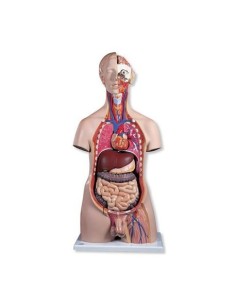

Scopri il Mondo dell’Anatomia con Modelli anatomici di Precisione

Modelli Anatomici Dettagliati per Ogni Necessità

Dal cranio in 22 parti con incastri magnetici ai modelli di colonna vertebrale, da quelli di articolazioni a quelli di cuore, ogni pezzo della nostra collezione è progettato per un’immersione totale nello studio dell’anatomia umana. I nostri modelli, realizzati tramite scansioni di ossa vere, garantiscono un’esperienza tattile autentica e una fedeltà di peso quasi identica agli originali.

Strumenti Didattici Innovativi per l’Educazione e la Pratica Medica

Essenziali per studenti e professionisti, i nostri modelli anatomici sono strumenti didattici che permettono di osservare le strutture anatomiche con precisione, eliminando la necessità di dissezioni o studi invasivi. Sono inoltre utili per spiegare ai pazienti le patologie, rendendo la comunicazione più efficace e risparmiando tempo prezioso.